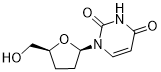

馬鞍山致研生物醫(yī)藥科技有限公司成立于馬鞍山市鄭浦港新區(qū)現(xiàn)代產(chǎn)業(yè)園。公司專(zhuān)注于生物小分子、醫(yī)藥中間體相關(guān)產(chǎn)品的研發(fā)和生產(chǎn),產(chǎn)品主要包括DNA亞磷酰胺單體、RNA亞磷酰胺單體、特殊單體以及按照客戶(hù)要求定制的RNA和DNA,并且公司提供定制合成等方面的研究服...

馬鞍山致研生物醫(yī)藥科技有限公司成立于馬鞍山市鄭浦港新區(qū)現(xiàn)代產(chǎn)業(yè)園。公司專(zhuān)注于生物小分子、醫(yī)藥中間體相關(guān)產(chǎn)品的研發(fā)和生產(chǎn),產(chǎn)品主要包括DNA亞磷酰胺單體、RNA亞磷酰胺單體、特殊單體以及按照客戶(hù)要求定制的RNA和DNA,并且公司提供定制合成等方面的研究服...